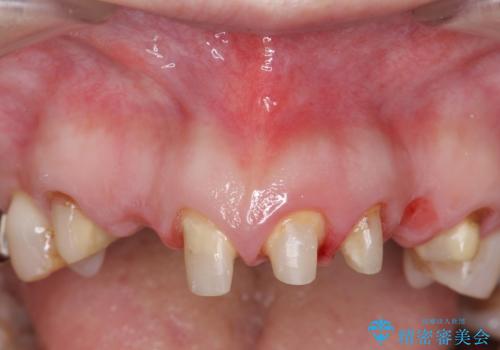

- 昔治療した前歯の被せ物の見た目を改善したいといらっしゃった方の症例です。

左上4番目の歯から右上3番目の歯まで計7歯のクラウンを除去し、オールセラミッククラウンによる補綴を行いました。

- オールセラミッククラウン…¥100,000×7、仮歯…¥10,000×7、ファイバーコア…¥20,000×5費用は治療当時の料金となります